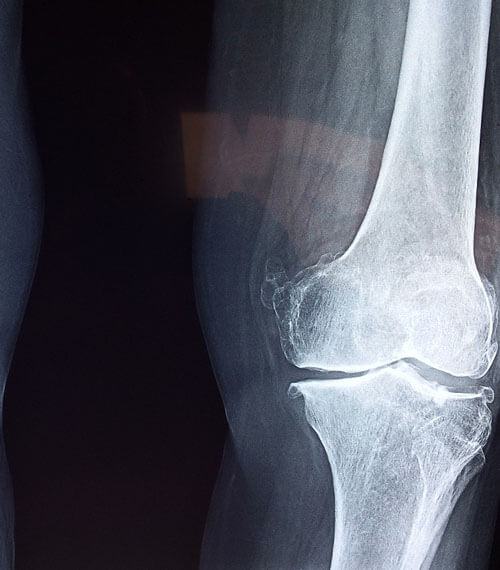

2. 퇴행성관절염

무릎을 많이 사용해 무릎 안쪽의 연골과

인대 등 주요 기관들이 닳아서 기능이 다하고

통증이 생기는 질환입니다.

주로 노년층에서 많이 나타나는 질환이지만

아주 가끔 젊은 층에서도 나타날 수 있고

몸무게나 잘못된 생활 습관 등으로 인해

발생하기도 합니다.

퇴행성관절염은 한 번 발생하면 지속적으로

통증이 나타나는 특징이 있기 때문에

초기에 적절한 진단 및 치료가 중요합니다.

해당 질환은 연골이 닳아서 없어지는 과정

이거나 없어진 이후이기 때문에

발생하고 초반엔 약물이나 물리치료 등의

비수술적 치료를 할 수 있지만

이미 많이 닳아서 없어진 경우라면

인공관절치환술, 무릎관절치환술 등의

수술적 치료가 진행될 수 있습니다.